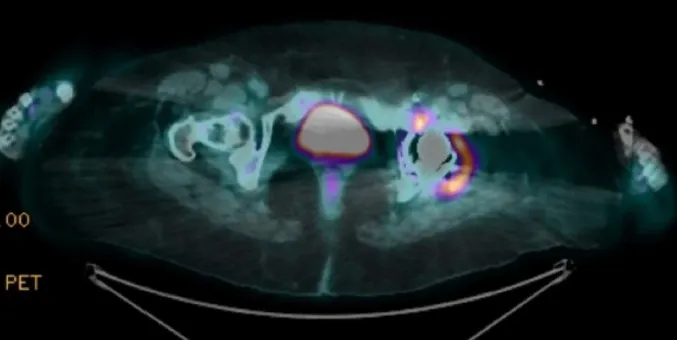

Hipercalcemia em DRC no pós-artroplastia: e se o vilão não for o PTH? Pistas discretas — 1,25(OH)₂D↑, ECA↑ e PET “quente” na prótese — apontam para ASIA por cimento ósseo. Acompanhe o raciocínio que faz o diagnóstico emergir e muda a conduta.

Valkercyo Feitosa

10 meses atrás